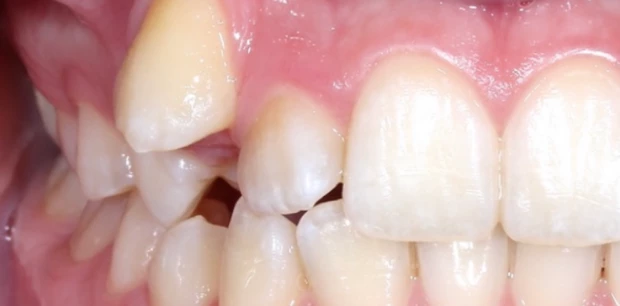

Ортодонтия

Ортодонтическое лечение элайнерами

Пациент И., 10 лет. Родители обратились с жалобами на неровные зубы сына. Проведено ортодонтическое лечение элайнерами. Лечение проводилось 1,5 года.